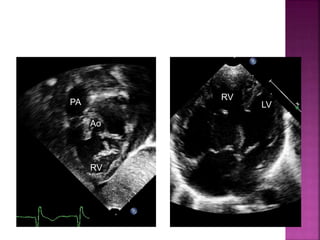

• subcostal coronal and sagittal planes; parasternal long axis

parasternal long axis

Ao

LV LA

Subcostal TEE

RV

PA